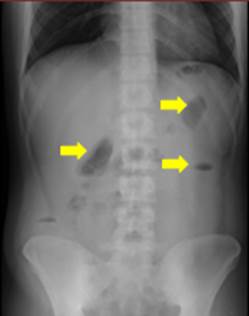

Se procede a realizar una valoración inicial con una serie de abdomen agudo, en la cual los Rayos X evidencian niveles hidroaéreos en los flancos del abdomen en bipedestación (Figura 1). A pesar de la presencia de gas distal, se realiza una ecografía de abdomen total que revela una imagen en la fosa iliaca derecha con ecogenicidad mixta, predominio líquido y medidas de 76,6 x 52,2 milímetros, con un volumen de 138,0 centímetros cúbicos, compatible con obstrucción intestinal en este nivel.